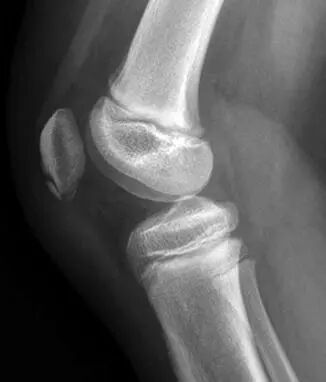

髌骨的骨化变异情况很常见。已骨化的髌骨可能呈颗粒状或结节状;它可能存在硬化区和透亮区。前方的透亮区以及前方表面的横向和纵向嵴尤其常见。垂直裂隙最为常见(图1)。

正常的副骨化中心可能是单个的,也可能是多个的,并且可能与髌骨分离,也可能不分离。